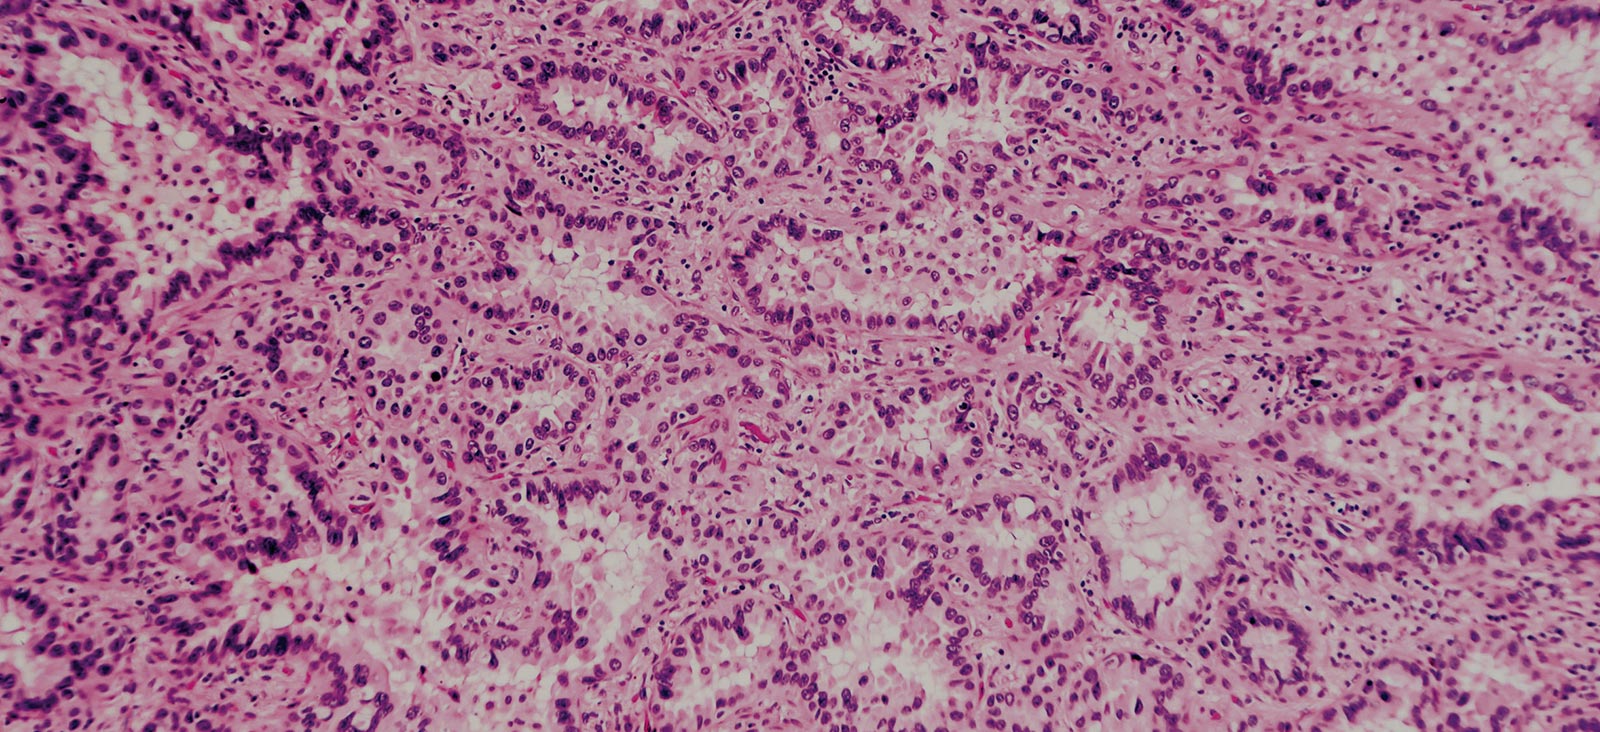

The treatment landscape of non-small cell lung cancer (NSCLC) has significantly advanced over the past two decades due to improved understanding of disease tumor biology, mechanisms of resistance, and earlier diagnosis. The widespread uptake of biomarker-guided targeted therapy has extended survival for patients in the metastatic setting, but continued research into new therapies and combination approaches is needed to broaden clinical benefit and further improve outcomes for patients with advanced lung cancer. [1]

Epidermal growth factor receptor (EGFR) inhibitors have proved to be an effective treatment for patients with EGFR-activating mutations. Since all NSCLC will eventually become resistant to single agent EGFR tyrosine kinase inhibitor (TKI) therapy, one area of ongoing research is how to overcome resistance to TKI therapy. [2-3]

Mutations in the EGFR tyrosine kinase are found in about 15% of NSCLC adenocarcinomas in the U.S. and observed more often in nonsmokers. [4] The decision to use an EGFR TKI is based on detection of these mutations using either solid tissue biopsies or liquid biopsies. [5] The underlying molecular mechanisms and signaling pathways contributing to TKI resistance in EGFR-mutant lung cancer are still being elucidated, but recent research has shown that inhibition of mutant EGFR elicits type I interferon (IFN)-I upregulation via an RIG-I-TANK-binding kinase 1 (TBK1)-IRF3 pathway. [2] Furthermore, inhibition of EGFR wild-type (EGFRwt) upregulates IFNs via an NF-κB-dependent pathway. [2]

Recent work by our team showed that inhibition of IFN signaling enhances EGFR-TKI sensitivity in EGFR-mutant disease and renders EGFRwt NSCLC sensitive to EGFR inhibition in preclinical models. They also observed that tumors with less IFN-I expression are more sensitive to EGFR-TKI therapy. These results suggest that IFN-I signaling is a central component of EGFR-TKI response and that combination treatment with an EGFR-TKI and IFN-neutralizing antibody might be viable for patients with NSCLC, but further clinical studies are needed to validate these results. [2]